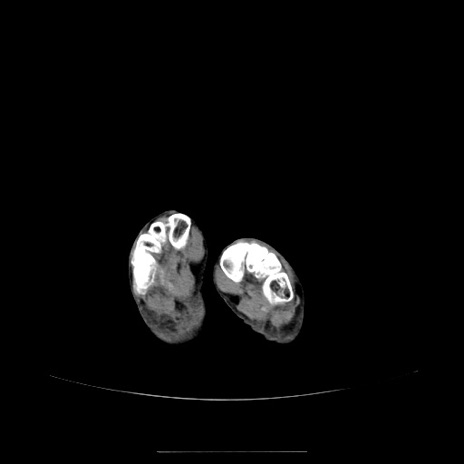

冠状断像

【症例】70歳代女性

【主訴】お腹が張る

【現病歴】1週間くらい前から腹部膨満の自覚あり。昨日夜から増悪したため、本日救急外来受診。

【身体所見】意識清明、BT 36.5℃、BP 165/106mmHg、HR 80bpm、SpO2 98%、腹部:膨満、軟、自発痛・圧痛なし、触診にて不快感あり、腸蠕動音:減弱

【データ】WBC 12600、CRP 1.04